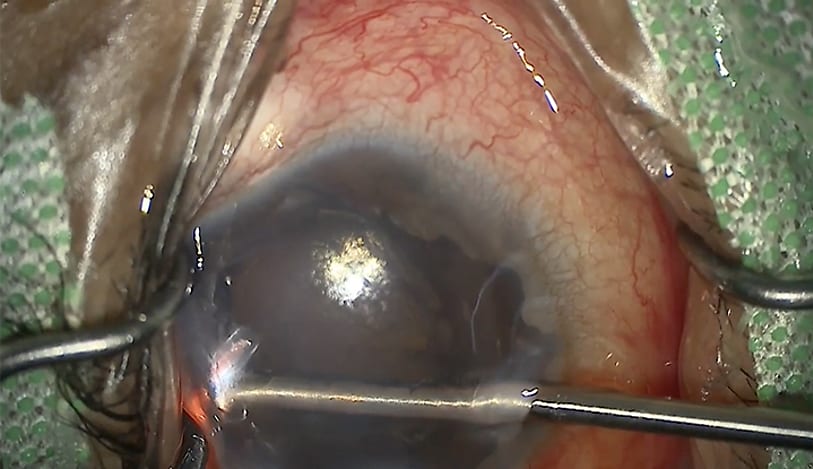

Xen Study Finds Ab Interno and Externo Approaches Equally Effective

February 23, 2026